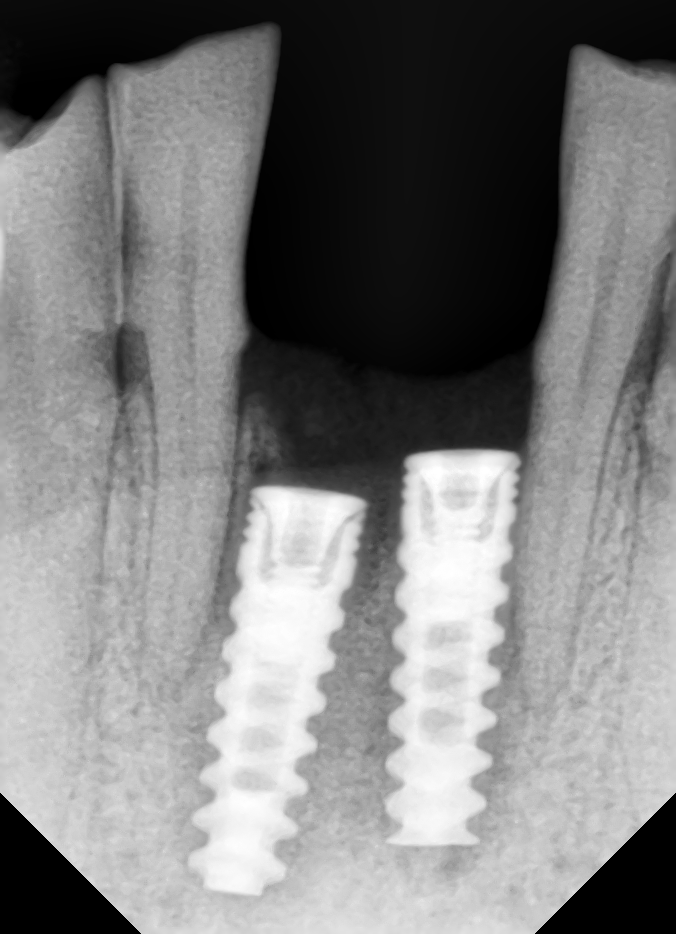

IDENTIFICAR IMPLANTE 25

BUENAS TARDES...EL IMPLANTE DEL 24 ES ZIMMER Y NECESITO SABER EL 25